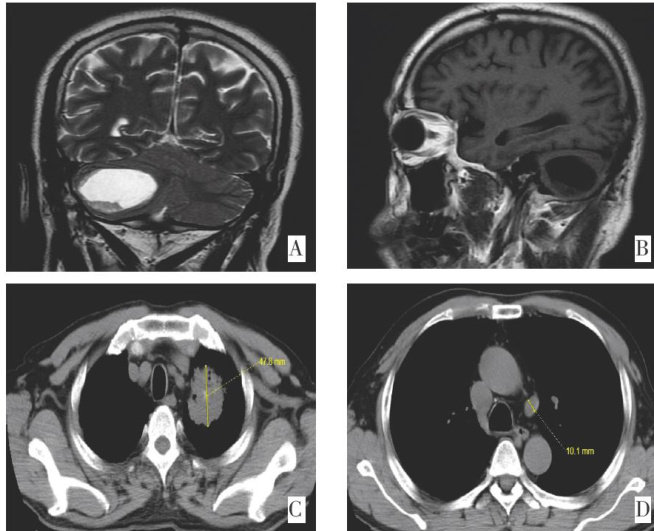

摘要:随着磁共振成像等影像学技术的不断发展,脑转移瘤的检出率越来越高。其中囊性脑转移发病率虽然远低于实性脑转移,但囊性脑转移瘤患者病情急,占位效应明显,是临床亟待解决的问题。既往文献报道囊性脑转移多见于乳腺癌和肺腺癌,特别是驱动基因阳性肺癌患者。该文报告1例以神经系统症状起病的小细胞肺癌囊性脑转移患者在多学科诊疗模式下获得临床治愈,在影像学动态评估以及微小残留病灶检测下避免过度治疗,延长生存期的基础上获得较高的生活质量。